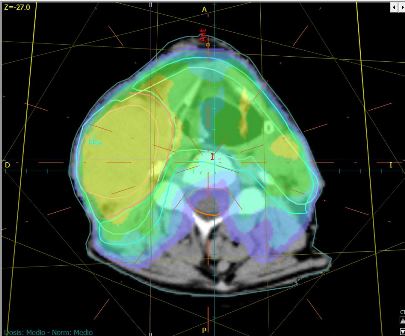

Radioterapia de intensidad modulada (IMRT)

La Radioterapia de Intensidad Modulada es una técnica moderna que permite mediante el uso de haces de radiación de intensidad variable, tratar múltiples volúmenes tumorales a diferentes dosis y en forma muy precisa, entregando baja dosis en el tejido sano durante cada fracción de tratamiento.

La IMRT es una modalidad aún más precisa que la radioterapia 3-D, ya que permite irradiar tumores con un mínimo daño al tejido sano mediante la utilización de diferentes incidencias de campos con intensidad de dosis no uniformes en el volumen tumoral, lo que nos permite la reducción del volumen de tejido sano expuesto a dosis altas de irradiación y escalar dosis en el tumor con mínima toxicidad aguda.

La técnica consiste en dividir el haz de tratamiento en cientos de pequeños haces independientes cada uno con intensidad variable e irradia al paciente desde ángulos y ubicaciones más favorables.

- Posibilita obtener distintos niveles de dosis en un mismo campo de irradiación, lo que permite maximizar la dosis en el volumen tumoral y minimizar la dosis en los órganos a riesgo; aumentando las posibilidades de control local y sobrevida disminuyendo las toxicidades agudas y crónicas.

- Permite aumentar dosis en zonas próximas a órganos críticos, que con la implementación de otras técnicas de radioterapia es imposible de lograr.